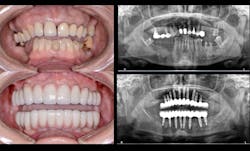

Whether it is an implant consultation for a single implant (figure 4), multiple implants, or full-mouth reconstruction, advanced 3-D software, such as the CS 3D Imaging software, offers you the ability to virtually plan the implant placement in regard to bone height, width, and density with respect to anatomical structures. Once planned, this information is reviewed with the patient in a clear and concise way that is easily understood (figure 5). In my experience, patients often state that they didn’t know that this type of technology was even possible within a dental office. Because of these reasons and more, I have found that case acceptance has gone up exponentially.

Figure 5: Virtual planning of immediate implant placement

In today’s practice, dental professionals should have imaging that can satisfy all their diagnostic needs. CBCT is an investment that generates a strong return, especially when it covers nearly every routine situation as well as more advanced clinical situations (figure 6). With the systems currently available, you can cost-effectively take the essential first step with 2-D panoramic views and investigate in depth with powerful 3-D imaging. As a result, you can offer and perform more procedures in your practice, improving the overall level of patient care.

Figure 6: A full-mouth implant reconstruction achieved with CBCT